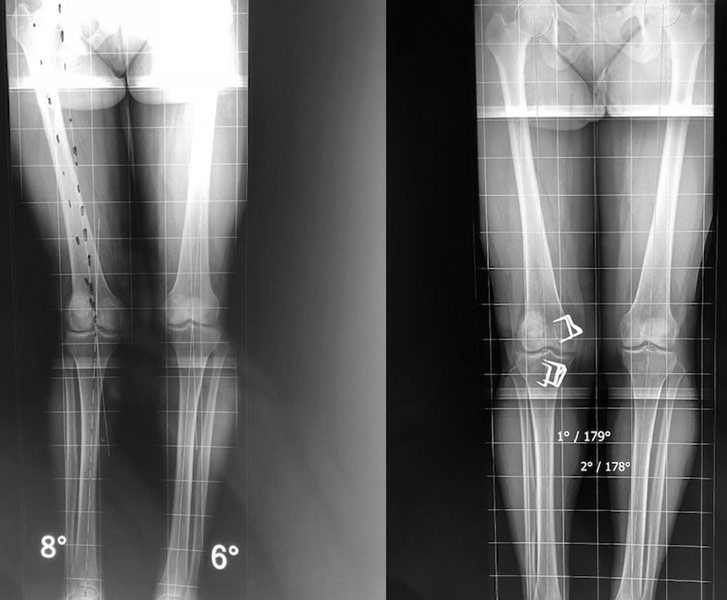

Déformation du genou en valgus (jambes en X), femme jeune (45 ans), ancienne handballeuse aux jeux de Séoul ; le fémur et le tibia sont déformés. Handicap majeur.

On réalise une double ostéotomie de varisation lors de la même opération, fémorale et tibiale, fixées avec des agrafes métalliques.

Double ostéotomie de vagisation lors de la même opération, au fémur par soustraction d’un coin d’os en externe, fixée avec une lame-plaque à 95° ; au tibia par ouverture interne (avec comblement par le coin d’os prélevé au fémur) fixée par une plaque.

Aucune douleur, aucune boiterie 5 ans après l’opération de ré-axation du genou.